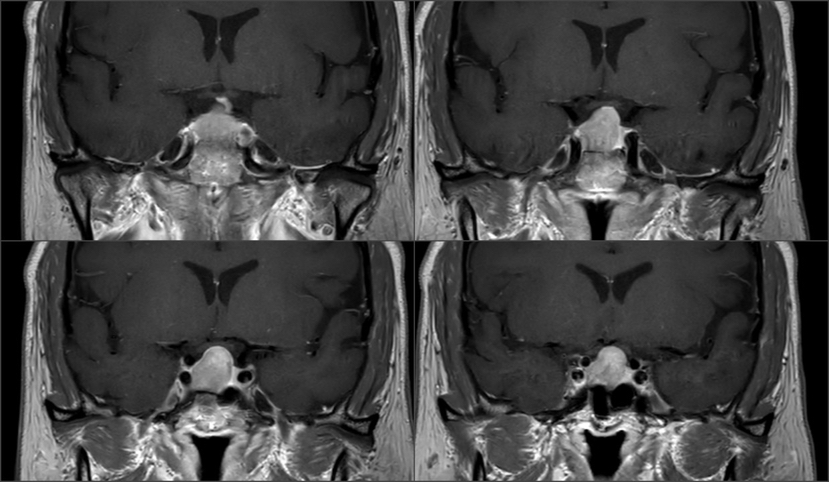

影像资料

Knosp1级肿瘤,鞍隔被肿瘤推挤向上,冠状位略呈“雪人征”,术中鞍隔可能塌陷 T2信号较为均质,考虑肿瘤有一定韧性 垂体柄偏向左侧,残存垂体左侧更多,鞍隔面、鞍底面亦有薄层受压垂体组织,术中需注意保护,亦有助于辨认肿瘤与垂体之间的分界面